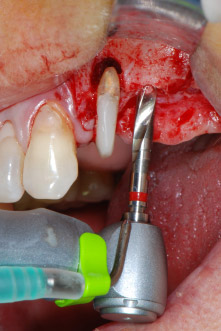

Implant beds were prepared at sites 25 and 26 with rotary instruments, used in a contra-angle handpiece with a 20 : 1 transmission ratio with an updated powerful implant motor (Implantmed, W&H) (Fig. 8).

The final preparation next to the sinus was again carried out with a piezoelectric instrument (Piezomed, insert S2).

Prior to implant placement, and following verification of an intact Schneiderian membrane (Fig. 9), the internal sinus floor was augmented at both implant sites by means of xenogeneic bone substitute material (Bio-Oss, Geistlich Biomaterials) (Fig. 10).